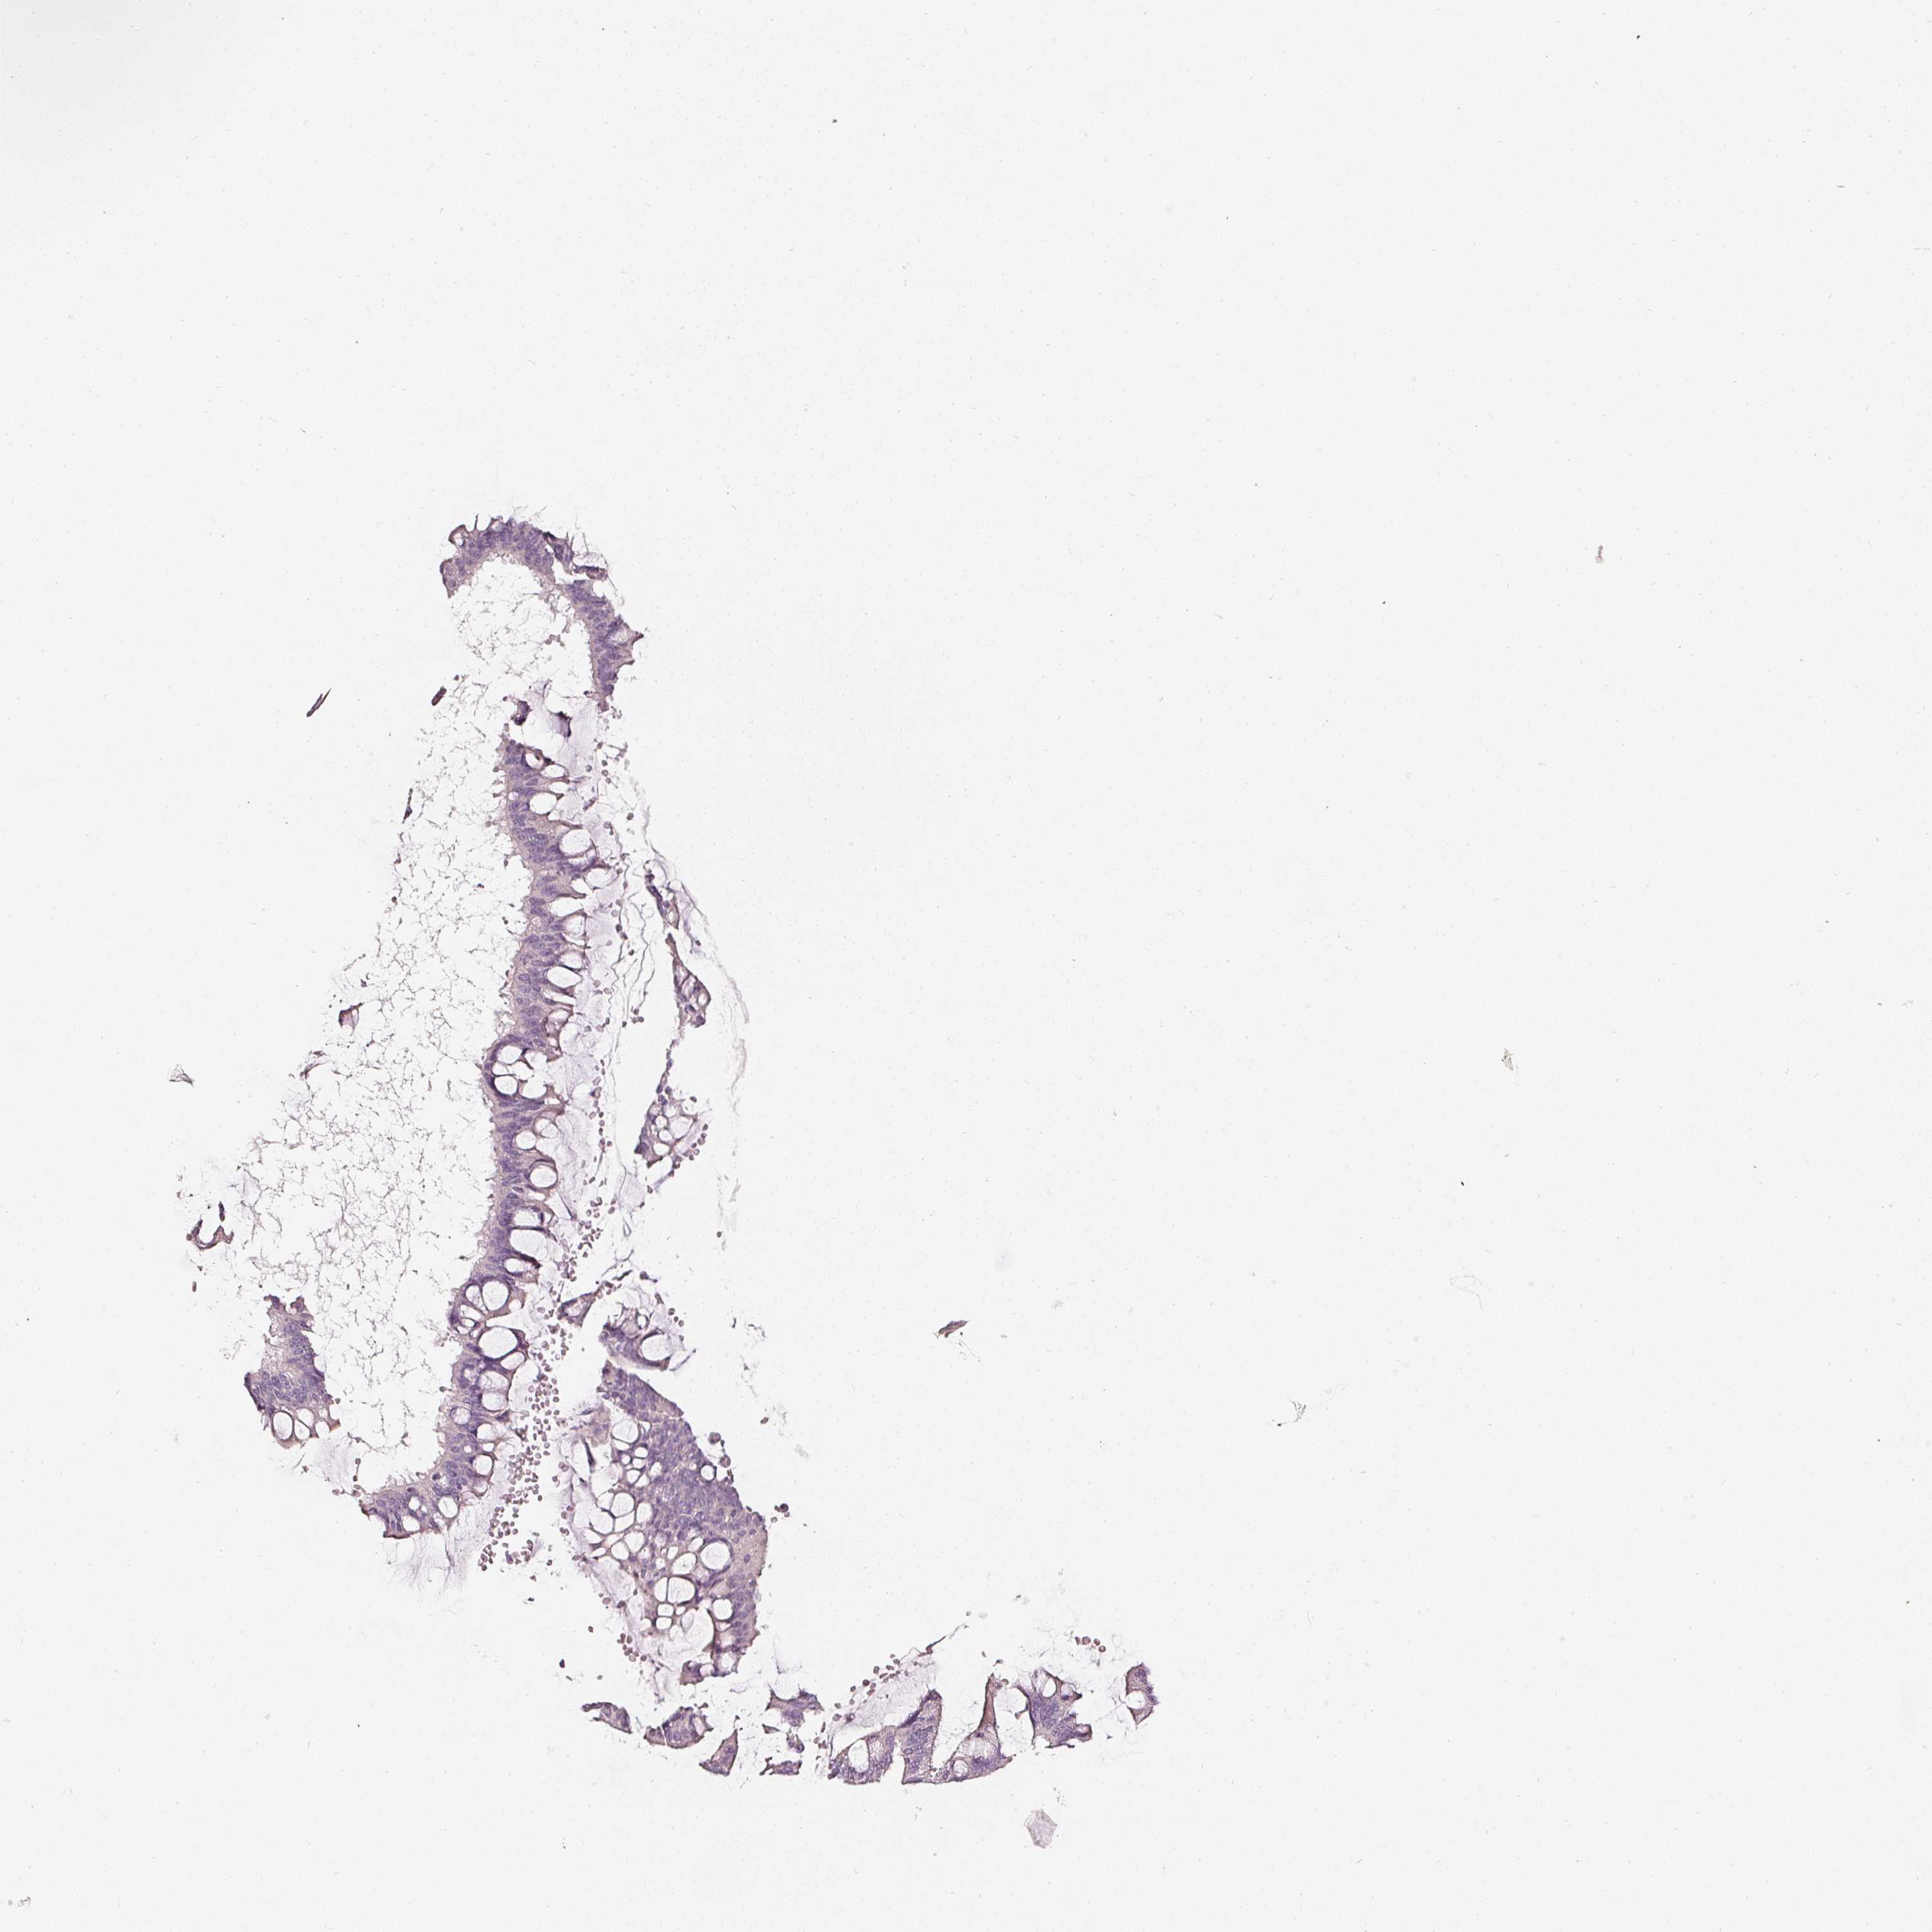

OVARIAN CANCER - Protein expressioni

A mouse-over function shows sample information and annotation data. Click on an image to view it in a full screen mode. Samples can be filtered based on level of antibody staining by selecting one or several of the following categories: high, medium, low and not detected. The assay and annotation is described here.

Note that samples used for immunohistochemistry by the Human Protein Atlas do not correspond to samples in the TCGA dataset.

Antibody stainingi

Antibody staining in the annotated cell types in the current human tissue is reported as not detected, low, medium, or high, based on conventional immunohistochemistry profiling in selected tissues. This score is based on the combination of the staining intensity and fraction of stained cells.

Each image is clickable and will lead to virtual microscopy that enables deeper exploration of all samples and also displays staining intensity scores, fraction scores and subcellular localization as well as patient and tissue information for each sample.

Cystadenocarcinoma, mucinous, NOS